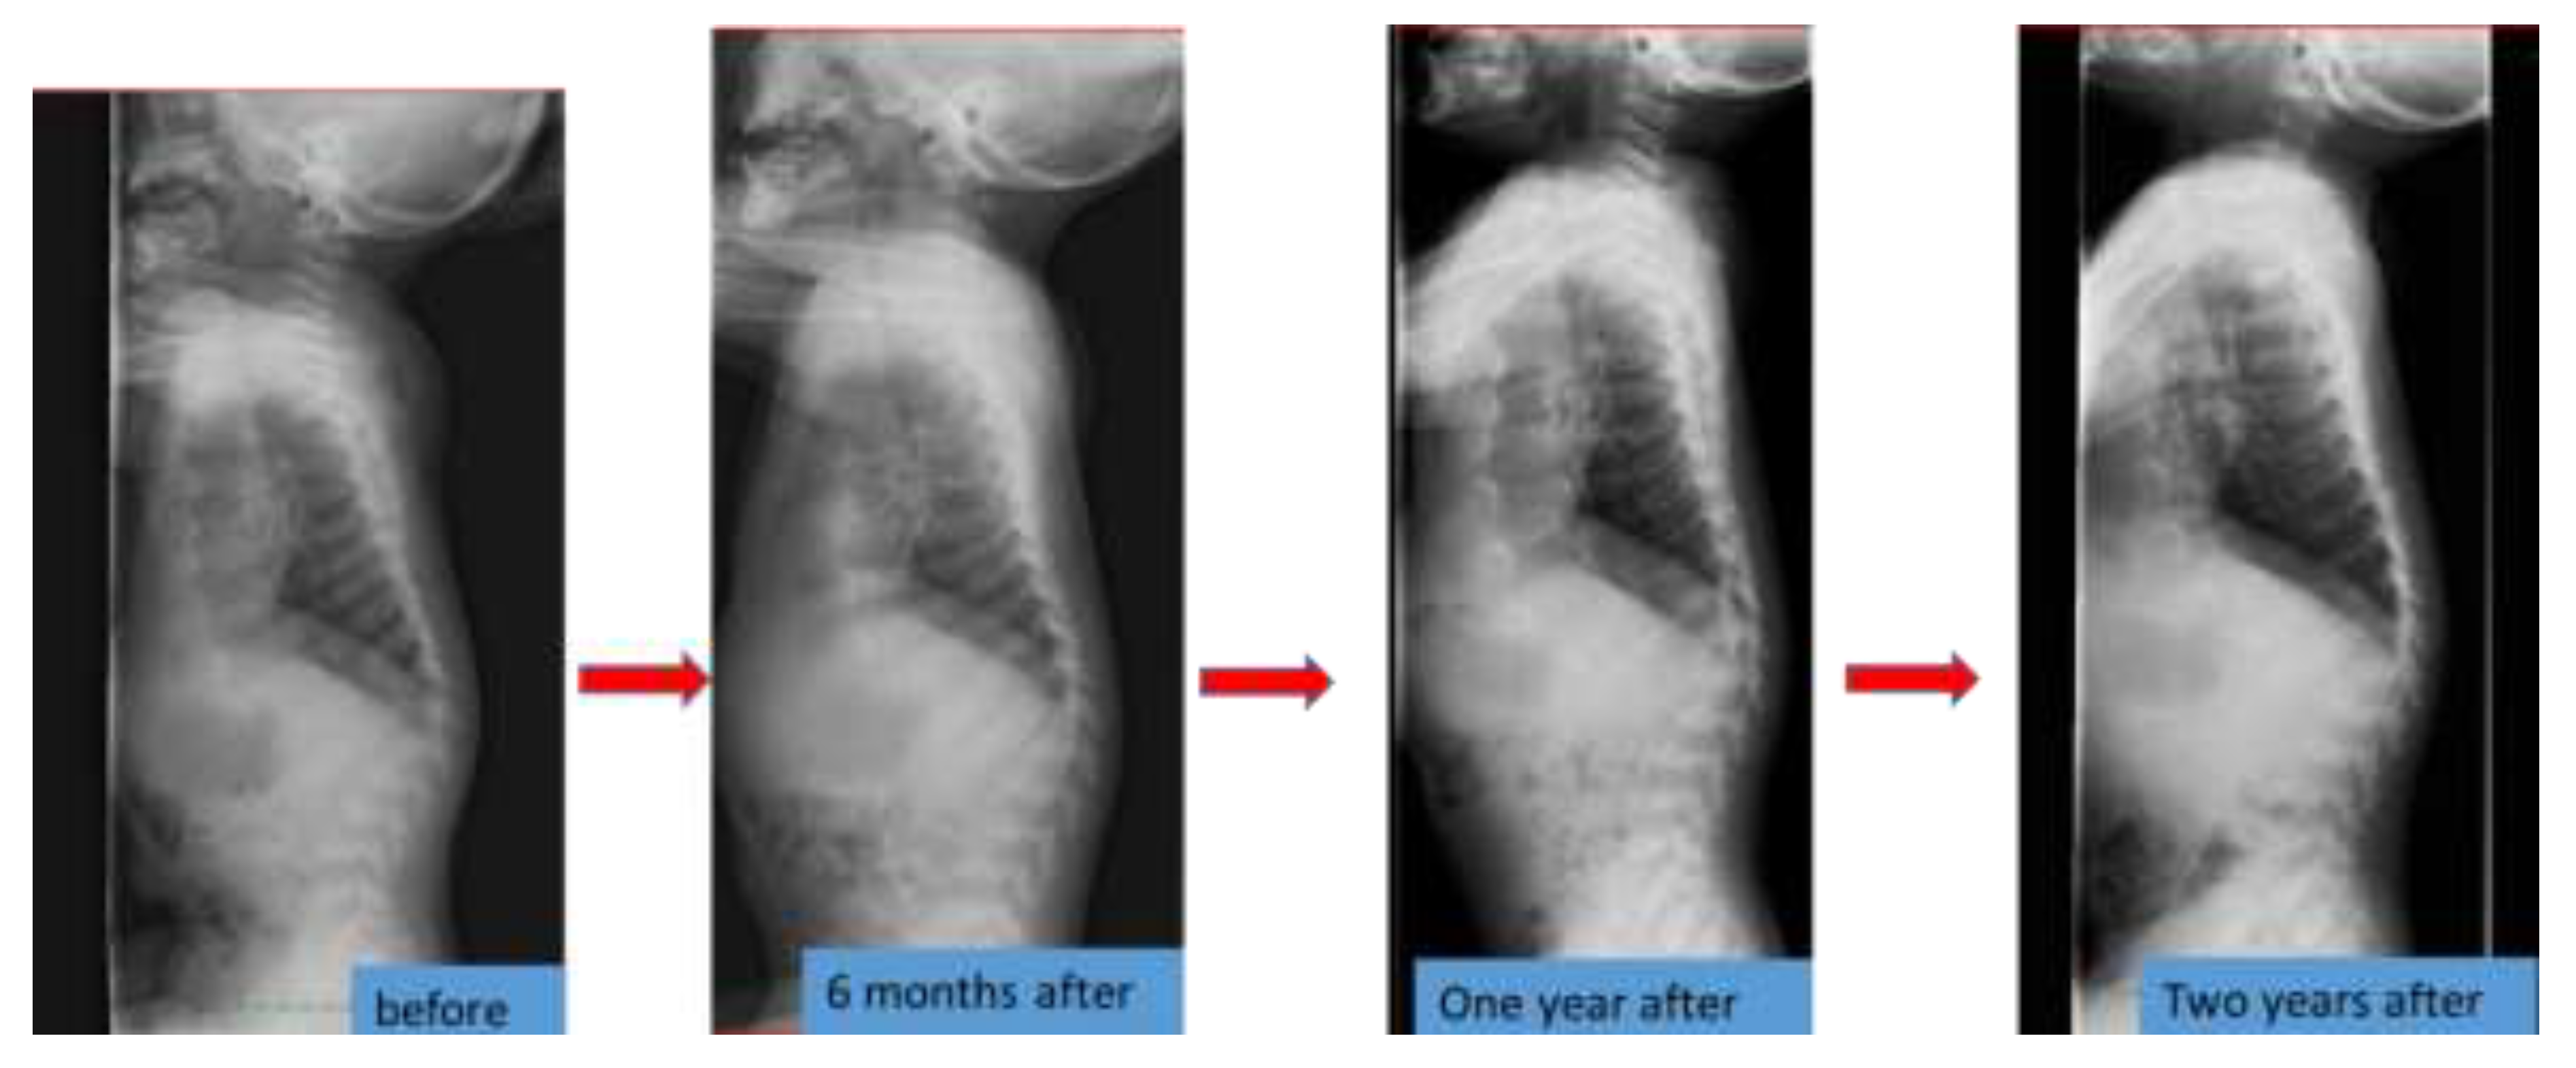

6.4. Spinal Lesions

| Kyphosis angle (degree) | 126 | 131 | 141 | 138 |